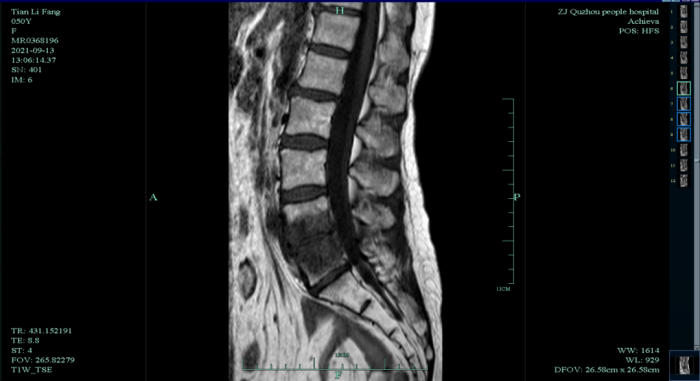

在家人的陪同下,田大嬸來到我院,感染科陳曉春醫(yī)生建議行磁共振檢查,檢查結(jié)果提示“腰4、5椎體異常信號影伴椎旁及腰大肌內(nèi)側(cè)軟組織腫脹,以椎體結(jié)核伴周圍寒性膿瘍形成首先考慮;腰椎退行性變;腰1/2、腰4/5椎間盤膨出;骶管囊腫?!?span>

經(jīng)抗結(jié)核藥物治療2個月后,患者腰痛明顯減輕,雙腿麻木消失,能自行下床行走??菇Y(jié)核治療4個月后,復(fù)查腰椎磁共振,提示病灶明顯吸收,病情好轉(zhuǎn)。